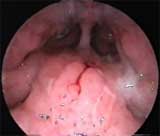

Вид аденоидных вегетаций III степени при осмотре задних отделов полости носа эндоскопом 0° (осмотр через левую половину носа).

Аденоидные вегетации III степени, блок задних отделов полости носа (риноскопия — эндоскоп 0°).